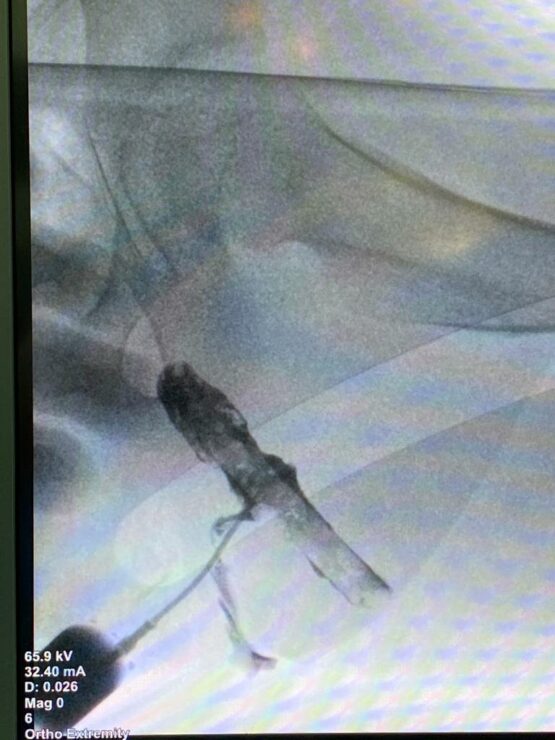

מכיוון שלא ידעו מה מקור הכאב, ערכו ברמב"ם מספר בדיקות, לרבות בדיקת אולטרסאונד עם חומר ניגוד, ובמהלכה נצפה העיפרון. "חקרנו כמה כיוונים, אך לבסוף הבחנו בפצע חדירה שהחל להזדהם באזור שרירי העכוז וחשדנו כי ההמצאות גוף זר בגוף הוא זה שגורם לזיהום ודלקות ולכאבים שמהם זה סובל", משחזר פרופ' אידלמן ומוסיף, "מעבר לכאב לא פשוט שאיתו ילד קטן צריך להתמודד, חשוב להבין שמדובר בחומר שמתעכל בגוף ועלול לסכן את הילד מכיוון שהוא מכיל חומר רעיל".

מרגע שהבינו את מקור הזיהום, הפעולה הייתה פשוטה יחסית – דרך פצע החדירה, נשלף הגוף הזר, אותו עיפרון שהיה בגופו של ש' חודשים ארוכים, ולאחר התאוששות קצרה ש' שוחרר לביתו כשצפויה לו החלמה מלאה.